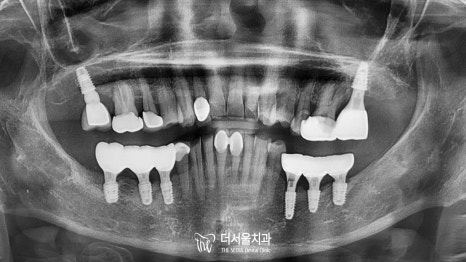

최종 보철을 올려드린 모습을 보면

텅텅 비어있던 곳이 새하얗고 예쁜 크라운으로

오밀조밀 잘 채워져 있습니다^^